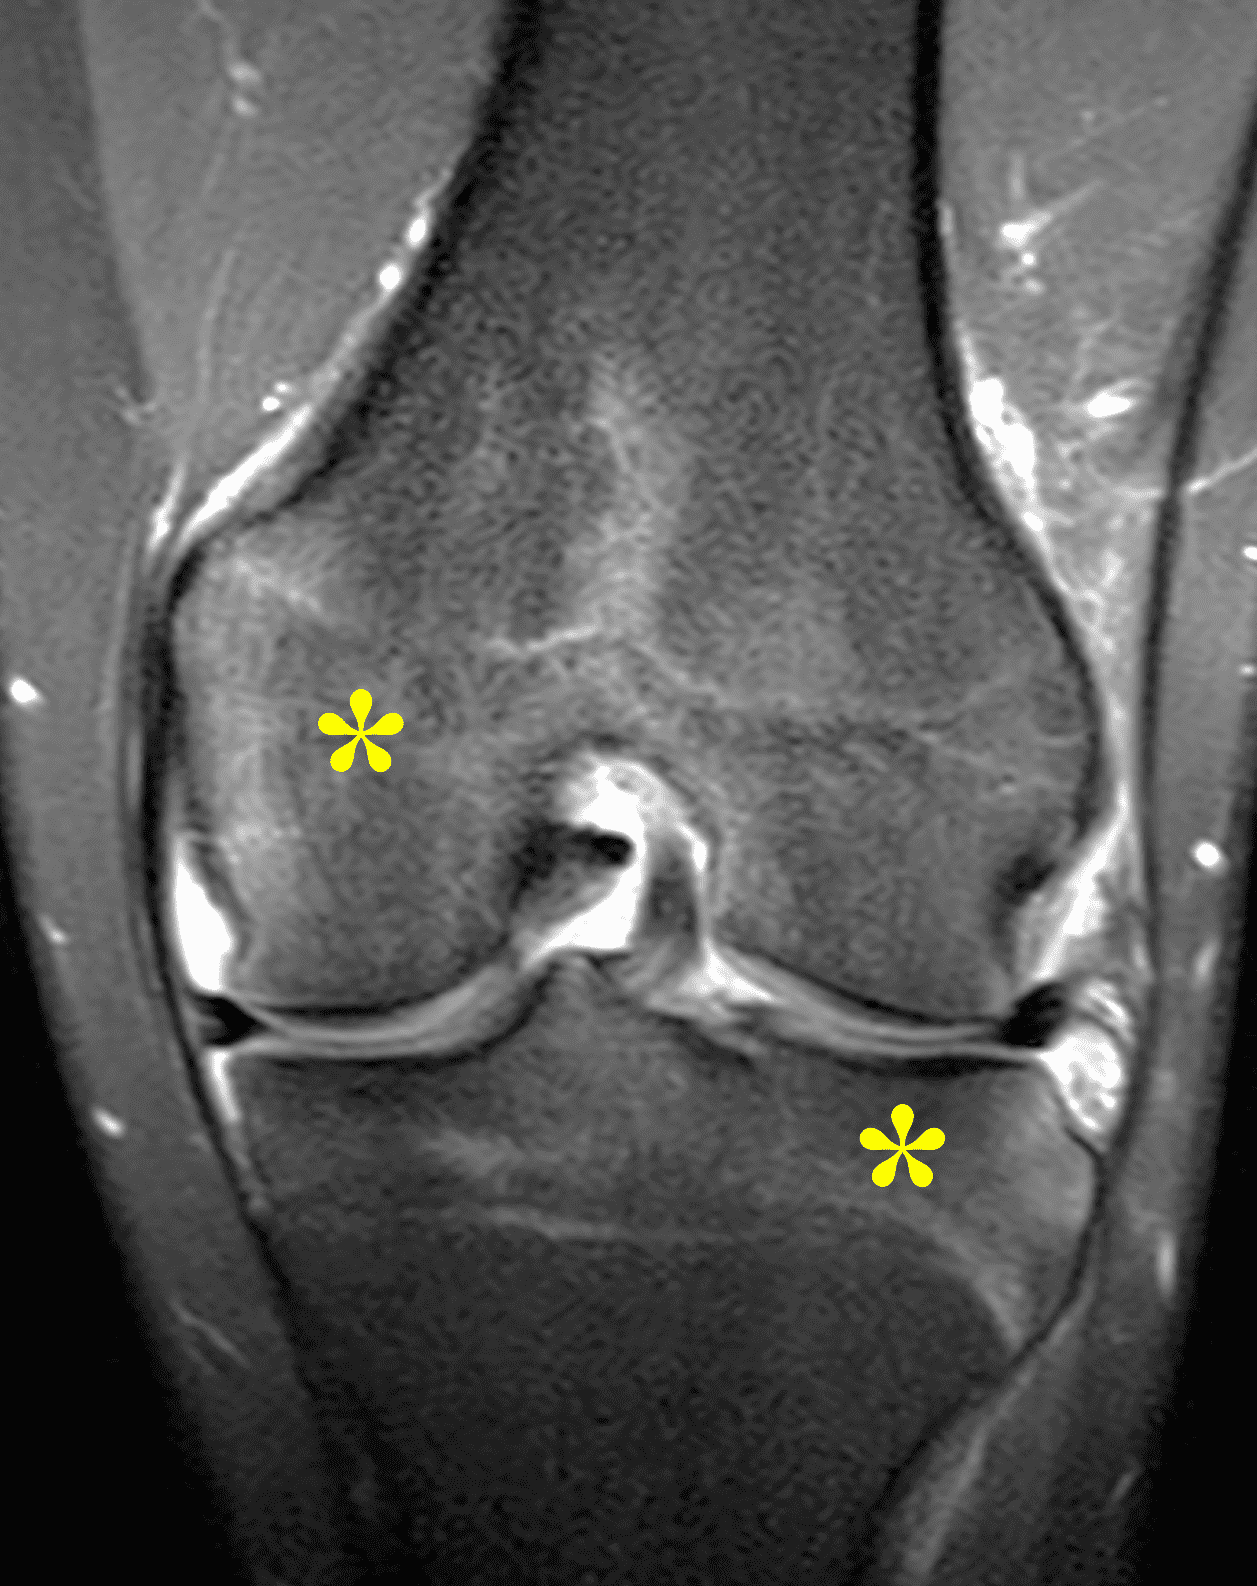

Figure 2: (2A) The coronal image shows a large effusion and severe hypertrophic synovitis (asterisks) in the knee. (2B) On the sagittal image the hypertrophic synovium (asterisks) involves the suprapatellar and infrapatellar recesses as well as the anterior and posterior intercondylar notch. A reactive lymph node (arrow) is present in the popliteal fossa. (2C) The axial image demonstrates myositis (arrows) involving the popliteus and peroneus longus muscles. Note the preserved articular cartilage, lack of erosions, and the absence of subcutaneous or marrow edema.